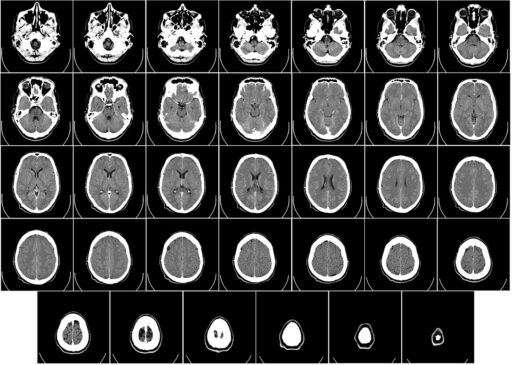

CT